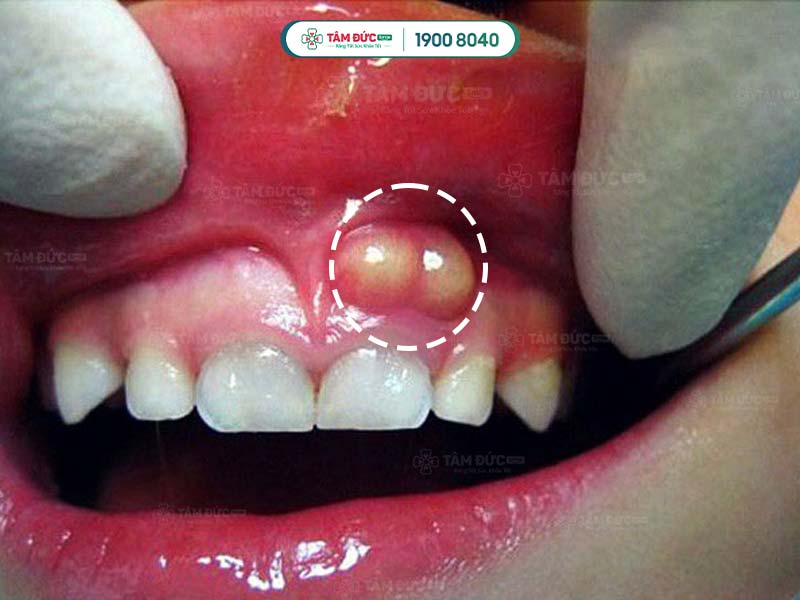

Nướu răng hàm trên bị sưng và tụ mủ

Viêm nướu làm sưng viêm và có mủ

Nhiễm trùng nướu răng cửa

- Áp xe răng: Đây là bệnh nhiễm trùng nghiêm trọng ở chân răng, có thể gây sưng, đỏ, đau nhức dữ dội, sốt, thậm chí là sưng mặt.